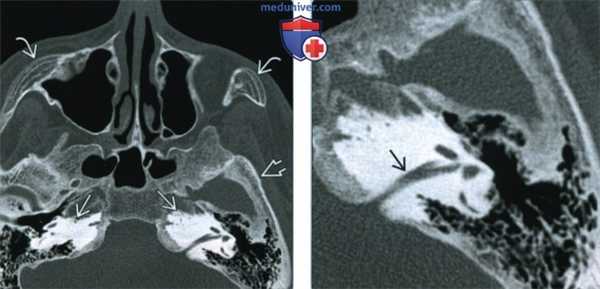

(Справа) При КТ костей основания черепа в аксиальной проекции наблюдается диффузный склероз всего основания черепа. Отмечается сужение полости среднего уха с обеих сторон. Также обратите внимание на поражение обоих внутренних слуховых проходов. У этого ребенка был диагностирован аутосомно-рецессивный остеопетроз. (Слева) При аксиальной КТ в костном окне основания черепа у молодого человека с аутосомно-доминантным остеопетрозом 2 типа наблюдается двусторонний плотный склероз височных костей и утолщение свода черепа, однако повышения плотности костей не отмечено. Обратите внимание на изменения обоих скуловых бугров типа «кости в кости» - остатки нерезервированных центров оссификации.

(Справа) При аксиальной КТ в костном окне у этот же пациента с остеопетрозом в проекции левой височной кости наблюдается протрузия патологической ткани пораженной кости внутреннего уха во внутренний слуховой канал.

(Слева) При рентгенографии в боковой проекции определяется диффузное утолщение свода черепа, основания черепа и височной кости, что характерно для более тяжелой формы остеопетроза (аутосомно-рецессивной).

(Справа) При КТ костей основания черепа в аксиальной проекции наблюдается диффузный склероз всего основания черепа. Отмечается сужение полости среднего уха с обеих сторон. Также обратите внимание на поражение обоих внутренних слуховых проходов. У этого ребенка был диагностирован аутосомно-рецессивный остеопетроз.

(Слева) При аксиальной КТ в костном окне основания черепа у молодого человека с аутосомно-доминантным остеопетрозом 2 типа наблюдается двусторонний плотный склероз височных костей и утолщение свода черепа, однако повышения плотности костей не отмечено. Обратите внимание на изменения обоих скуловых бугров типа «кости в кости» - остатки нерезервированных центров оссификации.